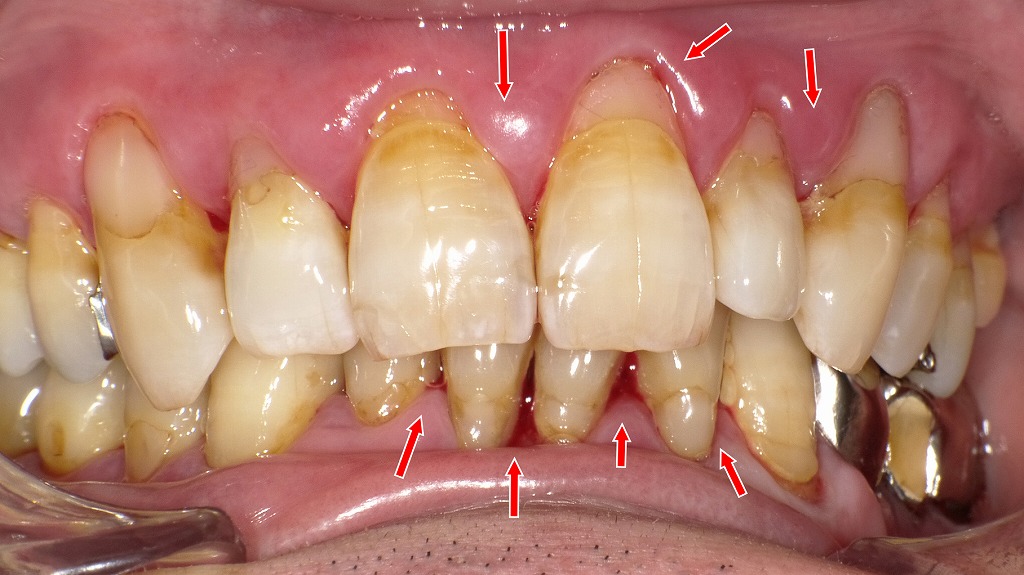

糖尿病と歯周病の悪循環と改善経過|炎症部位・磨き残し・治療効果が一目で分かる症例

糖尿病で歯周病が悪化しやすい理由|腫れ・出血・縁下歯石の典型例

① 正面写真:歯肉の腫れ・出血・プラークの付着が顕著

歯肉が全体に腫れ、軽度の自然出血が確認できる状態。

プラークと縁下歯石が歯周炎を助長し、糖尿病による治癒力低下で炎症が強く出ています。赤矢印で示されるのは、

- 歯肉の腫れ(発赤・膨隆)

- 軽度の自然出血

- 歯肉縁上のプラーク(細菌の塊)と着色

- 歯肉縁下の歯石が疑われる部位

糖尿病があると、血糖コントロール不良により歯肉の炎症が強まり、同じ量のプラークであっても腫れや出血が起きやすいのが特徴です。